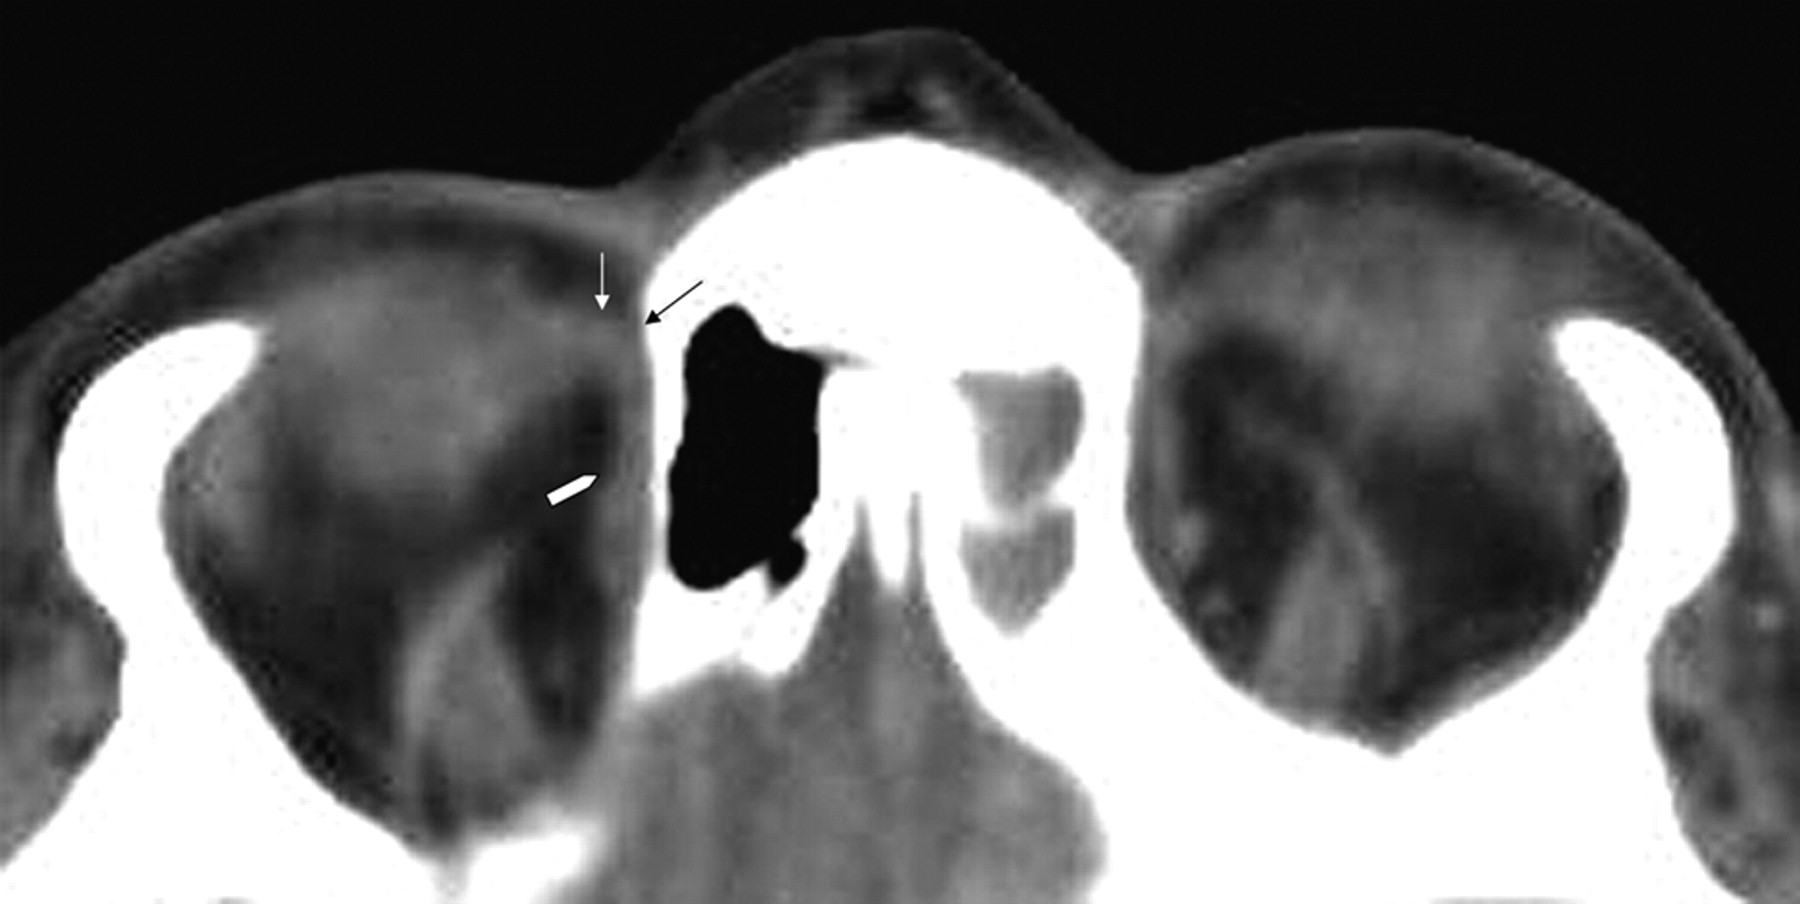

The course of the superior oblique tendon can be demonstrated on axial CT images. CT is unable to resolve fully the different components of the trochlea area; however, the combined structures are discernible (Fig 1). Axial MR imaging offers even less resolution, and both coronal CT and MR imaging allow visualization of only portions of the muscle belly (Fig 2).

Axial CT scan of the orbits demonstrates the course of the superior oblique muscle/tendon. The muscle extends anteriorly to the superomedial corner of the orbit (white arrowhead). Here it reaches the trochlea (black arrow), a fibrocartilaginous structure lying deep within the orbital fascia. Just before reaching the trochlea, the muscle becomes tendinous, and while passing through it, the tendon is compressed into a fibrous cord. Exiting the trochlea, the tendon runs inferiorly, posteriorly, and laterally (white arrow) to insert into the posterolateral portion of the sclera.